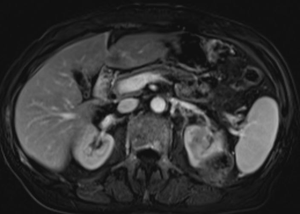

МР-диагностика образований почек